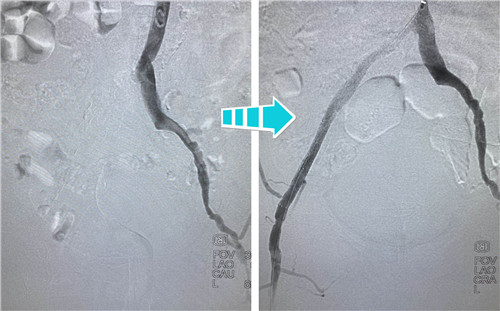

身經(jīng)百戰(zhàn)的放射科介入團隊,在南京鼓樓醫(yī)院血管外科王煒教授的指導(dǎo)下,決定為吳老先生行兩側(cè)髂血管成形術(shù)。手術(shù)當天,選擇經(jīng)左側(cè)肱動脈入路,置入90CM長鞘,在導(dǎo)絲指引下,小心翼翼地通過左側(cè)股總動脈狹窄段,給予球囊擴張,精確定位并植入支架,左側(cè)髂血管就此打通??紤]后期患者情況改善,可能還需要處理股淺動脈,專家們還預(yù)保留了股淺和股深開口。